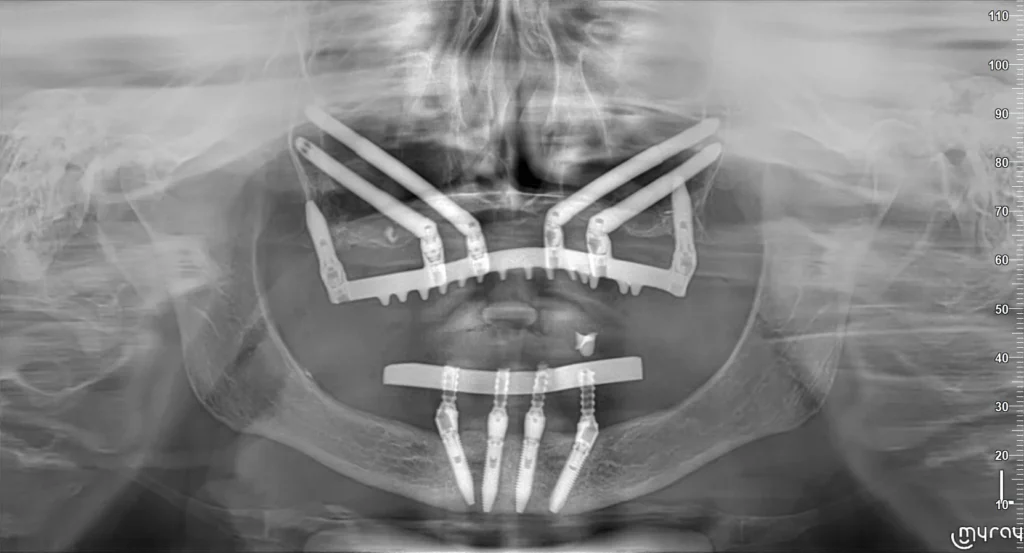

Un impianto dentale zigomatico è un tipo speciale di impianto dentale, significativamente più lungo e con un design leggermente differente rispetto ai suoi omologhi tradizionali. Mentre un impianto classico misura tipicamente tra i 8 e i 15 millimetri di lunghezza, gli impianti zigomatici possono raggiungere i 30-60 millimetri. Questa lunghezza extra non è casuale, bensì funzionale allo scopo per cui sono stati creati: bypassare completamente l’osso mascellare atrofico e ancorarsi saldamente nell’osso zigomatico, che è parte del complesso scheletrico facciale e, cosa fondamentale in questo contesto, mantiene solitamente un volume e una densità superiori anche in presenza di una grave perdita ossea nella mascella adiacente. L’impianto viene inserito attraversando la cresta alveolare (l’osso mascellare residuo, per quanto scarso) e la cavità del seno mascellare, per poi trovare stabile alloggiamento nella porzione più densa e resistente dell’osso zigomatico. È un ancoraggio strategico, solido e affidabile, che permette di sostenere una protesi dentale fissa (un ponte o una Toronto Bridge) anche in assenza totale o quasi di osso nel sito che normalmente accoglierebbe un impianto tradizionale. La loro funzione primaria, quindi, è quella di fornire una base stabile e immediata per una protesi fissa in pazienti che altrimenti dovrebbero sottoporsi a procedure complesse e lunghe come gli innesti ossei massivi, o rassegnarsi all’uso di protesi mobili con tutti i disagi che ne conseguono.

L’intervento di implantologia zigomatica è una procedura chirurgica complessa che richiede una preparazione meticolosa, un’esecuzione precisa e l’esperienza di un’équipe chirurgica altamente qualificata. Non è un intervento che può essere eseguito in uno studio dentistico generico; richiede una sala operatoria adeguatamente attrezzata, personale infermieristico specializzato e, spesso, la presenza di un anestesista per garantire il massimo comfort e sicurezza del paziente. La procedura inizia molto prima di entrare in sala operatoria, con una fase di pianificazione dettagliata. Questo include esami radiografici approfonditi, come la tomografia computerizzata (TC cone beam), che fornisce immagini tridimensionali ad alta risoluzione delle strutture ossee del massiccio facciale, inclusi la mascella, l’osso zigomatico e i seni mascellari. Sulla base di queste immagini, il chirurgo pianifica il percorso esatto che gli impianti seguiranno per raggiungere l’osso zigomatico, tenendo conto delle specificità anatomiche del paziente e della posizione ottimale per il supporto della futura protesi. In molti casi, si ricorre anche alla chirurgia virtuale e a guide chirurgiche personalizzate stampate in 3D per aumentare ulteriormente la precisione dell’intervento. L’intervento vero e proprio, che generalmente si svolge in anestesia generale o in sedazione profonda per garantire l’immobilità del paziente e un’esperienza priva di stress e dolore, prevede l’accesso chirurgico alla regione mascellare e zigomatica. Gli impianti, che sono molto lunghi, vengono inseriti attraverso il tessuto gengivale e l’osso mascellare residuo, seguendo il percorso pianificato, fino a raggiungere l’osso zigomatico, dove vengono fissati in modo stabile. A seconda della situazione clinica e del piano terapeutico, possono essere inseriti due o più impianti per lato.

L’intervento per l’inserimento degli impianti zigomatici è una procedura chirurgica che segue passaggi specifici e rigorosi, data la delicatezza dell’area anatomica coinvolta. Una volta che il paziente è sotto anestesia (generalmente generale per interventi estesi su entrambe le arcate, o sedazione profonda per casi più limitati), il chirurgo procede con l’accesso all’area mascellare superiore. Questo può comportare un’incisione nella gengiva per esporre l’osso mascellare sottostante e l’apertura di una “finestra” ossea nella parete anteriore o laterale del seno mascellare, a seconda della tecnica specifica utilizzata e dell’anatomia del paziente. La tecnica specializzata consiste nel preparare con estrema precisione il sito che ospiterà l’impianto, creando un canale che attraversa l’osso mascellare residuo e la cavità del seno mascellare per raggiungere l’osso zigomatico. L’impianto zigomatico viene quindi inserito lungo questo canale pre-determinato, fino a quando la sua porzione apicale (la punta) non si ancora saldamente nell’osso zigomatico, fornendo la stabilità primaria essenziale. È un passaggio critico che richiede grande abilità e precisione da parte del chirurgo per evitare strutture anatomiche importanti e garantire il corretto posizionamento dell’impianto. Dopo l’inserimento degli impianti (il numero varia in base al caso, ma tipicamente si usano 2-4 impianti zigomatici per lato nel mascellare superiore atrofico), le gengive vengono suturate. Nella stessa seduta, se è previsto il carico immediato, viene avvitata agli impianti una protesi provvisoria fissa, che il paziente manterrà durante il periodo di guarigione (osteointegrazione), che dura alcuni mesi, prima di ricevere la protesi definitiva. L’intero iter operatorio è pianificato digitalmente in anticipo per minimizzare i rischi e massimizzare il successo.

Le differenze tra impianti tradizionali e zigomatici sono sostanziali e riguardano diversi aspetti cruciali, dalla progettazione all’utilizzo clinico. La differenza più marcata è il **sito di ancoraggio**: gli impianti tradizionali si inseriscono direttamente nell’osso mascellare o mandibolare dove erano presenti i denti, mentre gli impianti zigomatici si estendono oltre l’osso mascellare atrofico per ancorarsi nell’osso zigomatico. Di conseguenza, la **lunghezza** è molto diversa: gli impianti tradizionali misurano tipicamente meno di 20 mm, mentre gli impianti zigomatici sono significativamente più lunghi, potendo superare anche i 50-60 mm. Questa differenza di lunghezza e ancoraggio determina le **indicazioni cliniche**: gli impianti tradizionali sono utilizzati quando c’è sufficiente osso nel sito del dente mancante, mentre gli impianti zigomatici sono la soluzione primaria nei casi di grave o gravissima atrofia del mascellare superiore, dove l’osso alveolare è insufficiente. Un’altra differenza fondamentale è la **necessità di innesti ossei**: nei casi di moderata perdita ossea, per gli impianti tradizionali potrebbe essere necessario un innesto minore. Per i casi di atrofia severa che richiederebbero impianti tradizionali (ma con innesti massivi), gli impianti zigomatici spesso consentono di evitare completamente queste procedure di innesto esteso. Infine, la **complessità chirurgica** è nettamente superiore per gli impianti zigomatici, che richiedono tecniche chirurgiche avanzate, pianificazione 3D e l’intervento di chirurghi con esperienza specifica, a differenza dell’implantologia tradizionale che, pur richiedendo precisione, è una procedura più standardizzata.